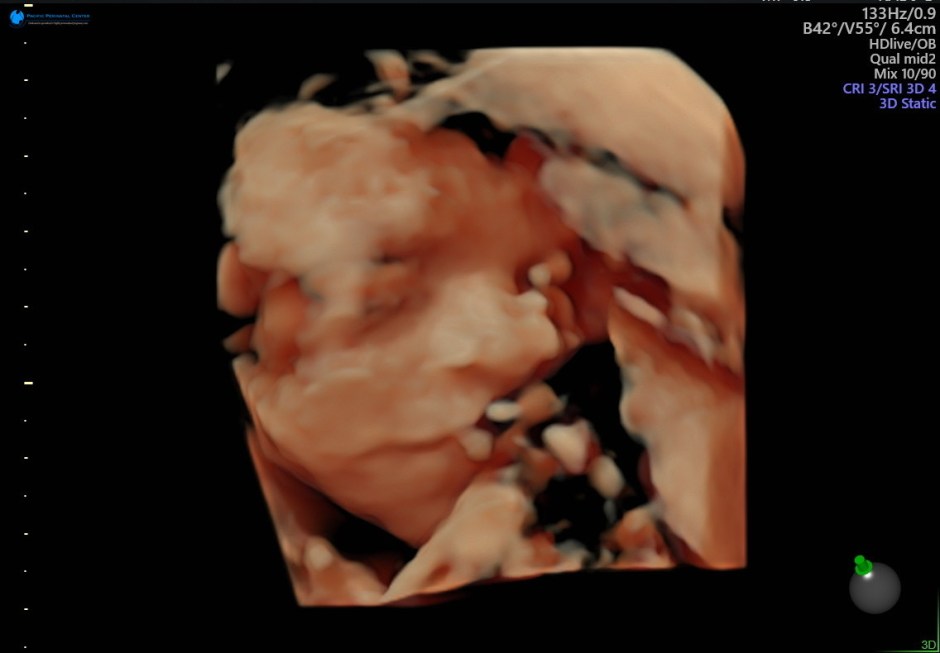

“Eh?” her husband said, half-deaf, half-snoring, and half-asleep. She leaned into his ear and spat out each word as crisply and loudly as she can: “I. CAN’T. FIND. MY. MASSSSSSSSSK!!!” “Oh,” he said, and they both fidgeted about looking for her missing mask, elbows and feet sticking into my space while I tried to sleep. She lost her mask at least three times during the flight. It also didn’t help that my baby was super active throughout the flight, practicing break-dancing or water polo or whatever it is it’s doing in there.

And then the baby kicked. Rolled. Air-guitared and danced.

I put both hands on my belly, and the baby responded to my touch, dancing wilder. And for the first time, I felt a deep emotional and spiritual connection to my unborn child. We experienced this trip together. We witnessed the work of God and His people together. We received blessings together.